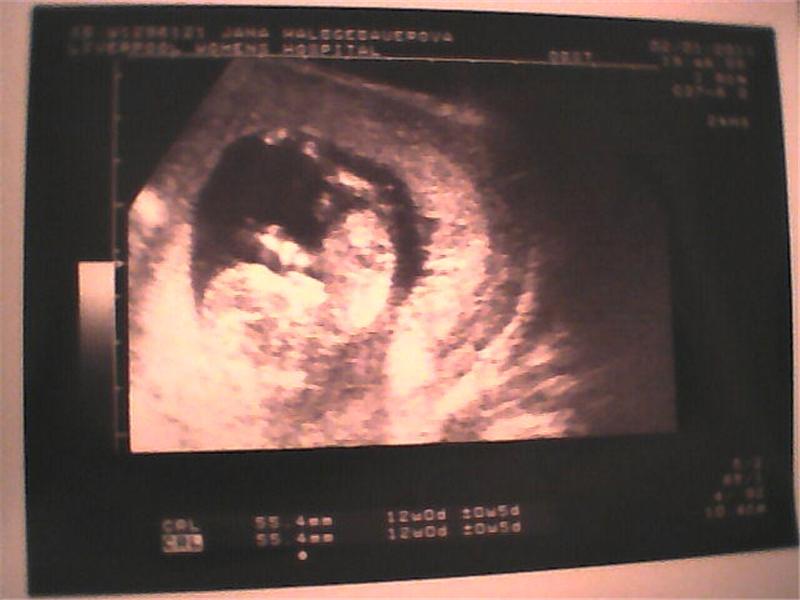

Muj malej mrnousek